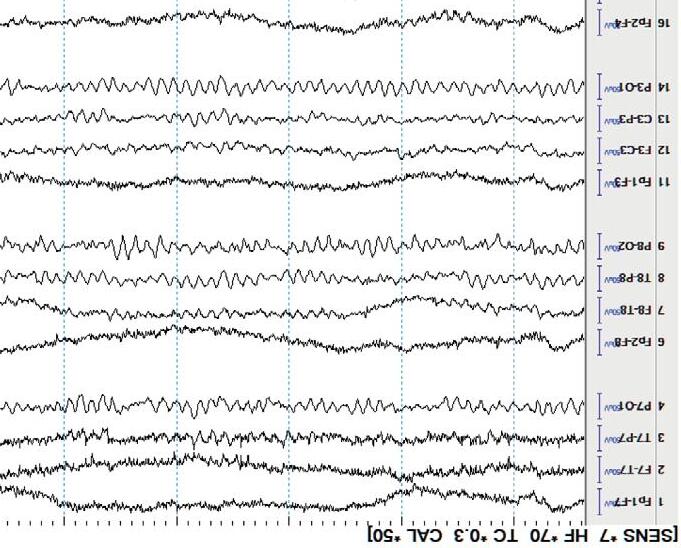

Display(Parameters) Atypicalbedsidedisplayusingalongitudinalbipolarmontageisshownin Figure1.3(a). Variationstothisformatexist.Commonly,theleftandtheright temporalchainsarestackedtogetherfollowedbytheleftandrightparasagittal chains.Thismakesiteasytocomparethetemporalandparasagittalregionsof bothhemispheresforasymmetry.Readersshouldknowthatthetemporal regionsarealsothemostepileptogenicsofocusingonthesechannelsyields results!Thetopbarofarecordingshowsthesensitivity,filtersettings,and timebase.

Mostdisplaysshow10or15secondsperpageofEEG. Figure1.5 showsa typicaldisplayusingthelongitudinalbipolarmontagewithexcessivemuscle artifactbefore(a)andafter(b)applicationof30Hzhighfrequencyfilter.

Figure1.5(a) EEGwithHFFsetto70Hz.